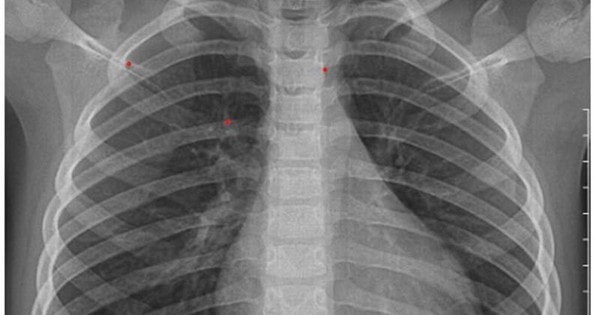

Bé 3 tuổi ở Hà Nội đối diện với loạt biến chứng nguy hiểm do cúm B từ dấu hiệu nhiều trẻ em Việt mắc phải

Bệnh nhi nhập viện do biến chứng cúm B với các triệu chứng sốt cao 38,5°C, ho có đờm, nghẹt mũi, sổ mũi. Gia đình cho dùng thuốc hạ sốt, kháng sinh... nhưng tình trạng không cải thiện.